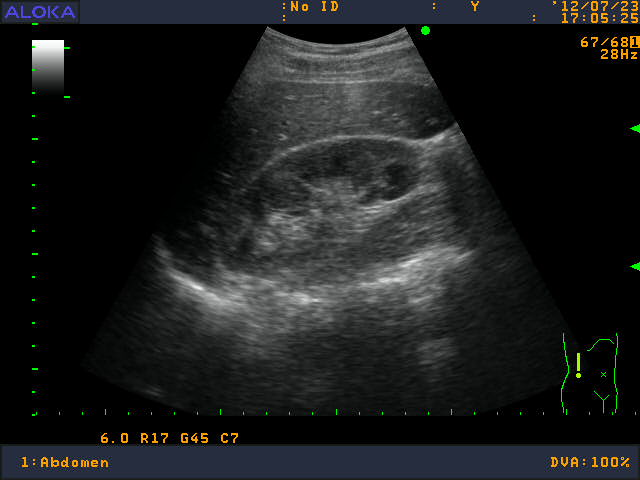

Клинические симптомы дают врачу возможность заподозрить у пациента острый или хронический пиелонефрит. Для подтверждения заболевания необходимо пройти дополнительные методы обследования.

В клиническом анализе крове определяется воспалительная реакция - лейкоцитоз со сдвигом формулы влево, повышение СОЭ. Результаты биохимического анализа крови укажут на почечную недостаточность в виде (определение мочевины, остаточного азота). Общий анализ мочи обнаруживает увеличение лейкоцитов в моче вплоть до пиурии. При бакпосеве мочи на питательную среду определяется наличие конкретного возбудителя - бактерии или простейшего. Полимеразно-цепная реакция (ПЦР) дает возможно определить этиологический агент, если он является внутриклеточным паразитом, например, хламидии.